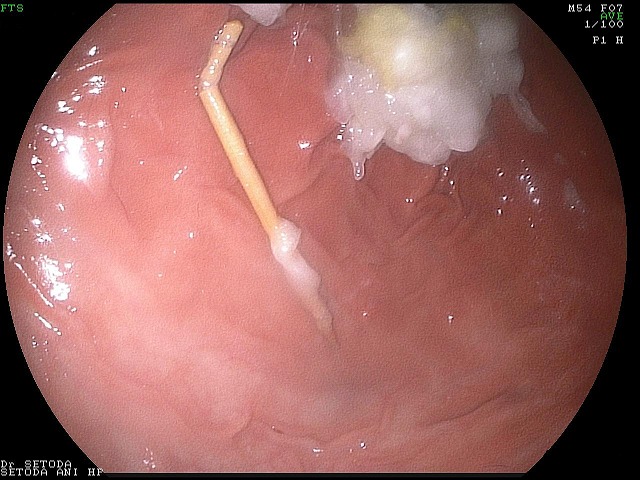

いったん引きだして、胃の中でつまようじの状態を調べてみると一部折れ曲がっています。

MAE00006.jpg

胃の中からつまようじを取り出す際に、胃や食道に傷をつけないように取り出すために、この折れ曲がった部分を持って、取り出すことにしました。